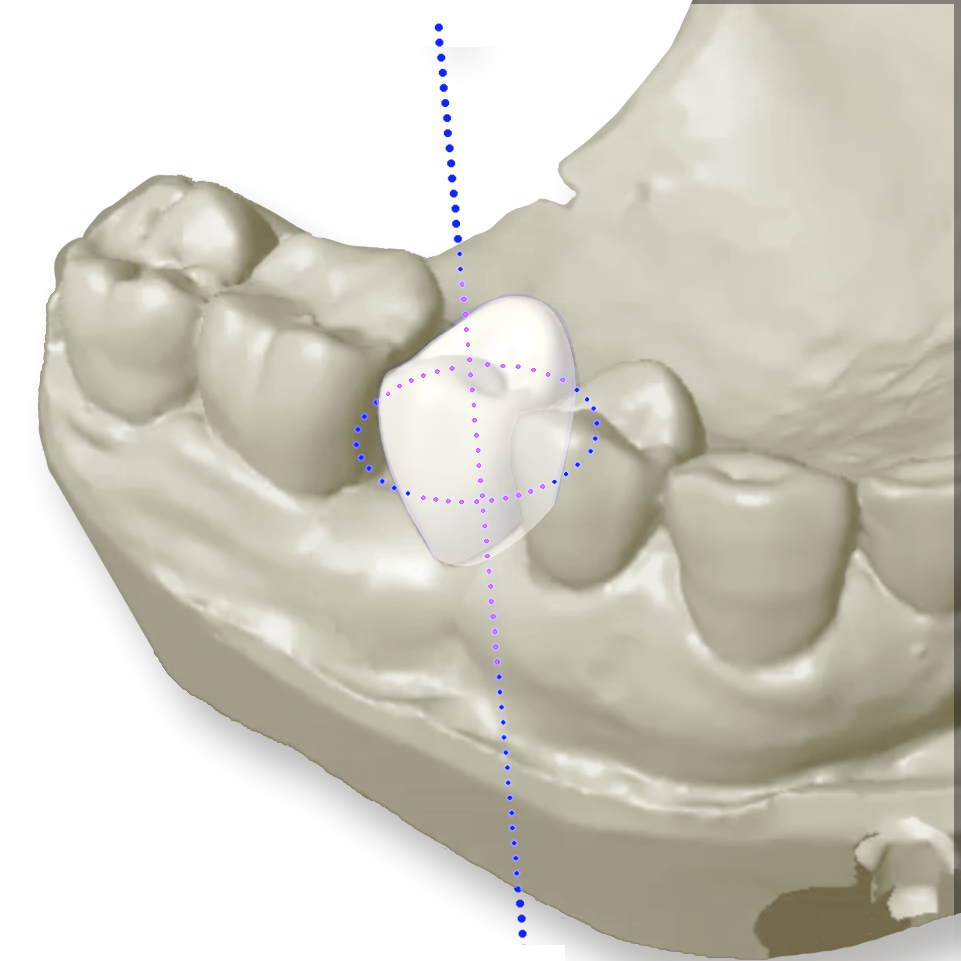

En tant que chirurgien-dentiste, vous savez que la précision du positionnement implantaire est essentielle pour garantir la pérennité de vos traitements et le confort de vos patients. Grâce à la chirurgie guidée, vous bénéficiez d’une approche numérique avancée qui optimise le positionnement tridimensionnel des implants, en tenant compte à la fois de l’environnement tissulaire et du projet de réhabilitation prothétique. Cette méthode améliore la précision chirurgicale, réduit les risques de déviation et favorise des interventions moins invasives, offrant ainsi des suites opératoires optimisées pour les patients.

- Une précision accrue : Positionnement tridimensionnel optimal des implants, respect des structures anatomiques et meilleure stabilité primaire.

Chirurgie Guidée Complète : un contrôle total du positionnement implantaire

- Guidage intégral : tous les forages et la pose de l’implant sont réalisés à travers le guide chirurgical.

- Protocole ULTIMATE G42 & G52 : pas besoin de réducteurs intermédiaires, les forets assurent un guidage direct ultra-précis.

- Compatible avec les implants In-Kone® et twinKon®, et intégrée aux principaux logiciels de planification implantaire.